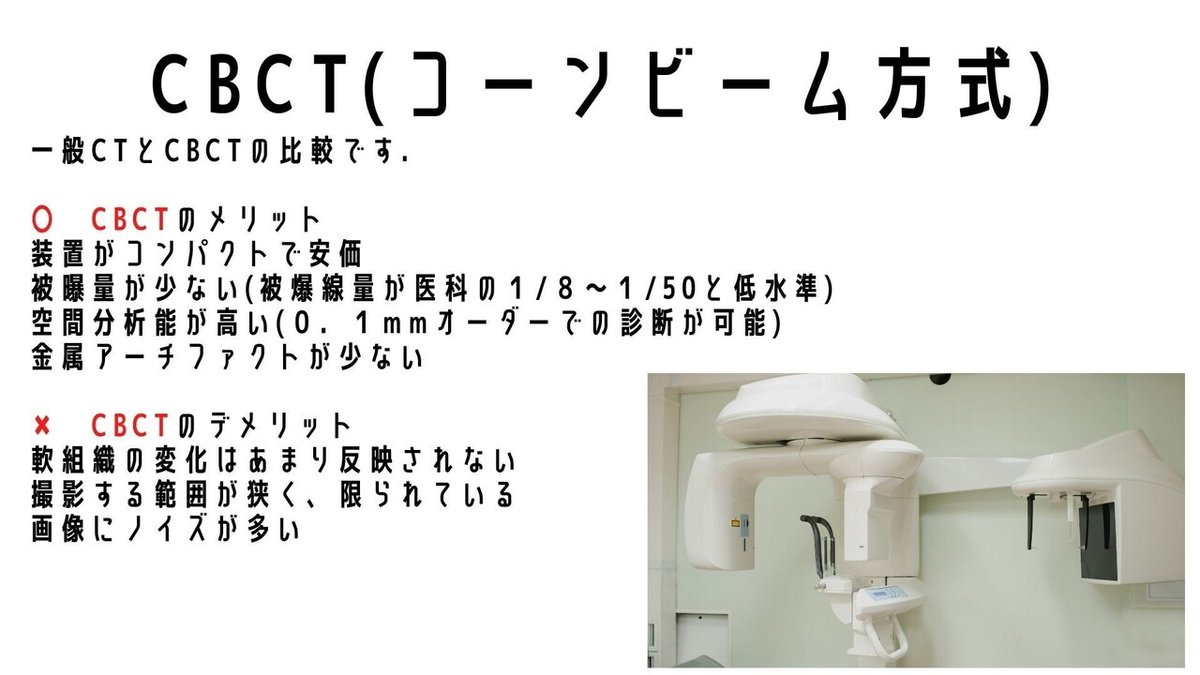

CBCTについて

医科と同じCTですが

方式や被ばく量に大きな違いがあります

・ファンビーム方式(一般CT)

一般の医科で行われている

・コーンビーム方式(歯科用CT)

歯医者でよく導入されている

コーンビーム方式と比較され

低被ばく量そして検査の簡易化を

考慮されてきており

Ta-Wei Yang(2021)らの発表でも

舟状骨骨折には

CTよりもCBCTが代替となる検査法として

台頭してくるといわれています

私見ではありますが

日本では,一般的なCTでまかなえる以上

CBCTは浸透しないと思っています

悲しいですが😂